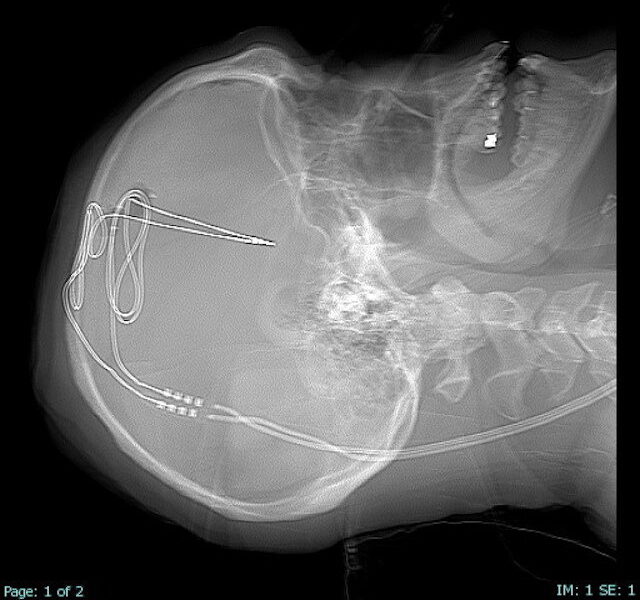

Pirmoji operacija atlikta Vakarų Virdžinijos universiteto ligoninėje. Pro skylę kaukolėje įvestas 1 milimetro skersmens elektrodas, siunčiantis elektrinius impulsus į smegenų sritį, kuri atsakinga už impulsus ir savikontrolę. Po raktikauliu implantuota baterija, medikai galės nuotoliniu būdu stebėti smegenų aktyvumą ir reguliuoti srovės stiprumą – daugiau ar mažiau stimuliuoti sritį, atsakingą už centrinę atlygio sistemos dalį. Įprastai potraukis narkotikams darytųsi vis stipresnis, tačiau smegenų implantas turėtų padėti reguliuoti potraukį.

Smegenų implantai išbandomi gydant priklausomybę nuo narkotikų. WVU nuotr.